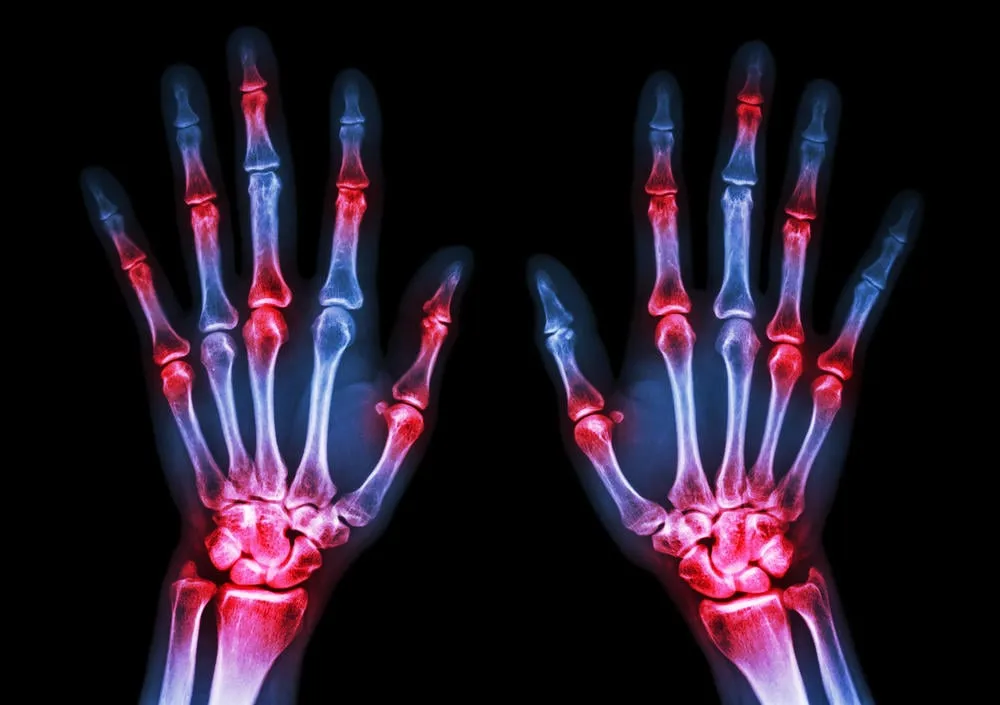

Les fractures du poignet sont fréquentes à partir de 50 ans puisque les os deviennent plus fragiles. Mais il est difficile de s'en remettre facilement et elles occasionnent d'importantes douleurs. Voici les 7 conseils de Medisite pour les éviter.